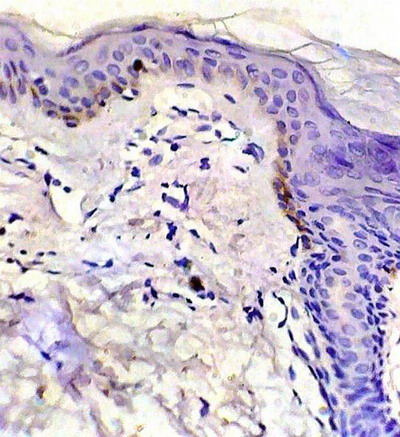

bcl-2 expression

-After treatment: increased bcl-2 expression in basal and suprabasal layers was observed in all specimens while lymphocytes showed marked decrease in bcl-2 positivity in 6 samples and negative staining in 4 samples (fig 6).

Fig 4: Control skin showing moderate bcl-2 expression. (ABC, Meyer s HX counter stain x 400)

Fig 6: After treatment with NB-UVB, increased bcl-2 expression in basal keratinocytes and marked decrease in bcl-2 positivity in dermal lymphocytes. (ABC, Meyer s HX counter stain x 400)

The low level of bcl-2 expression in LP lesions before treatment is in agreement with other authors [4,20]. Similar results were reported in oral LP [2,16,18]. The low expression of this anti-apoptotic protein might promote apoptosis of keratinocytes in LP. Hussein et al reported [4] that the low bcl-2 expression in the face of apoptosis of basal cells suggests the concomitant loss of other pro-survival molecules or increase in the pro-apoptotic molecules in the lesions of LP. Boyd et al [20] suggested that the low expression of bcl-2 in LP might indicate that bcl-2 is not prominently involved in epidermal changes in LP and the role of other members of this oncogene family needs to be elucidated. The increased expression of bcl-2 after NB-UVB treatment may be attributed to restoration of normal basal activity in the healing lesions. It is well known that in normal skin the actively proliferating cells of basal keratinocytes typically express bcl-2 which protects them against apoptotic stimuli [24].

On the other hand, the strong expression of bcl-2 in dermal lymphocytes in lesions of LP before treatment inhibits the apoptosis in lymphocytes that strengthens cell-mediated immune process causing chronicity of the disease [22]. After treatment with NB-UVB, the marked decrease in bcl-2 expression leads lymphocytes to undergo apoptosis which might contribute to healing of the lesions [25].